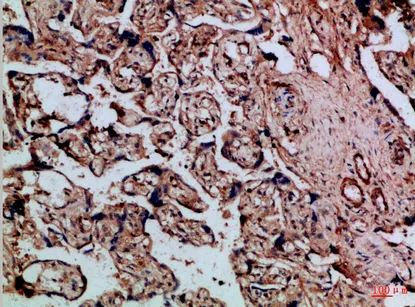

Mammaglobin A Rabbit Polyclonal Antibody

Cat: APRab13614

Size1:50μl Price1:$118

Size2:100μl Price2:$220

Size3:500μl Price3:$980

Size2:100μl Price2:$220

Size3:500μl Price3:$980